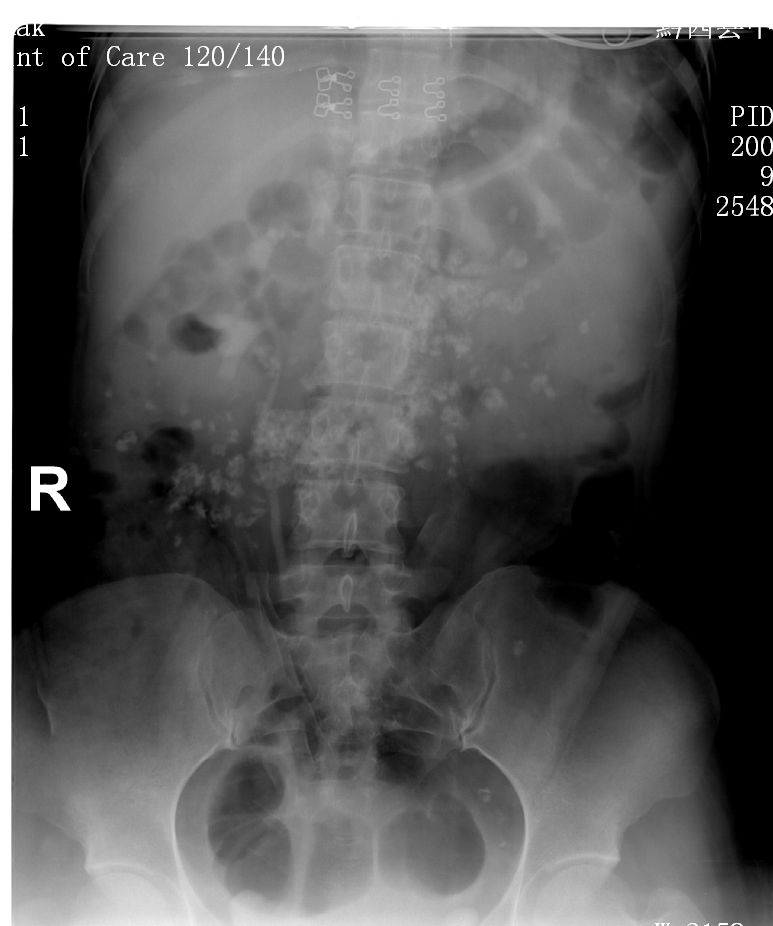

标题: X6299:请问这是淋巴结钙化吗?

在排除肠道内容物后可考虑腹部肠系膜淋巴结钙化可能。

右侧双肾畸形。

肠系膜多发淋巴结钙化。

肠系膜多发淋巴结钙化,支持。需排除肠道内容物

这是做的ivp? 肠道准备不大好   建议做完后直接做个增强看看

除肠系膜多发淋巴结钙化外寄生虫卵钙化也不能排除。

多发性肠系膜淋巴结钙化?肠道内高密度异物?泛影葡胺造影剂污染??